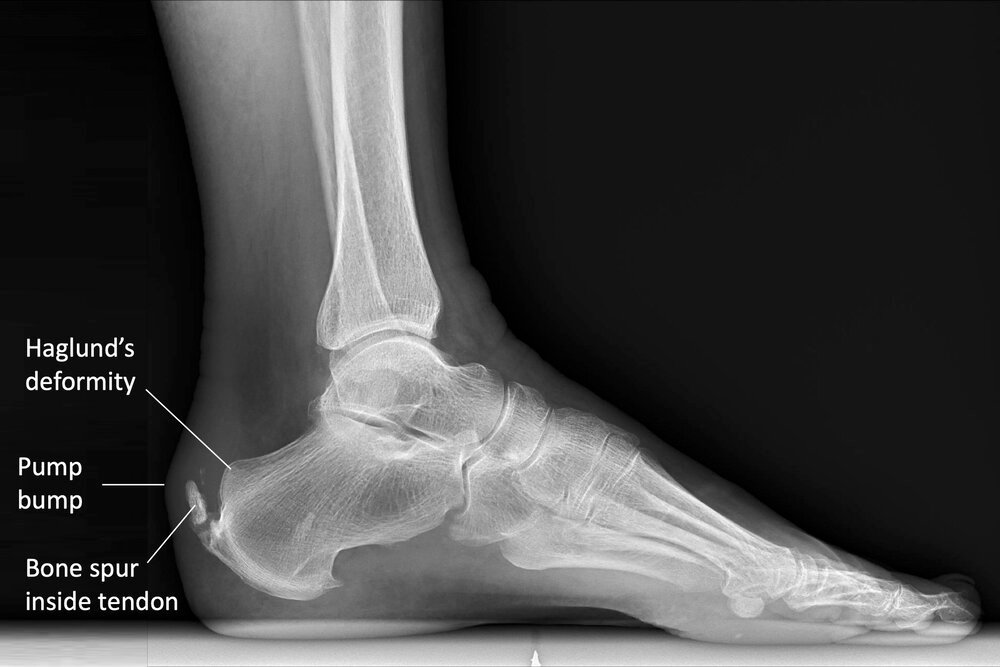

Imaging for Insertional Achilles Tendonitis

Insertional Achilles tendonitis on x-ray

- X-rays : X-ray imaging can help visualize any bone spurs or calcifications in the area of the Achilles tendon attachment.

- Ultrasound and MRI : Both ultrasound and MRI can provide detailed information about the condition of the tendon and assess the extent of degeneration and inflammation.